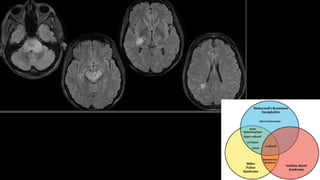

Nível de Consciência Transitório:

- Recuperação (Total ou parcial)

- Estado Minimamente Consciente

- Estado Vegetativo (falta prolongada de reação e alerta por disfunção intensa dos hemisférios

cerebrais, mas preservação suficiente do diencéfalo/ T.E. 🡪reflexos autônomos e motores e os ciclos

de sono-vigília conservados)

- Morte Encefálica

Obs: Síndrome do Encarceramento: Lesão isquêmica na Ponte 🡪 tetraplegia, mas

preservação do nível de consciência, além de certa movimentação ocular